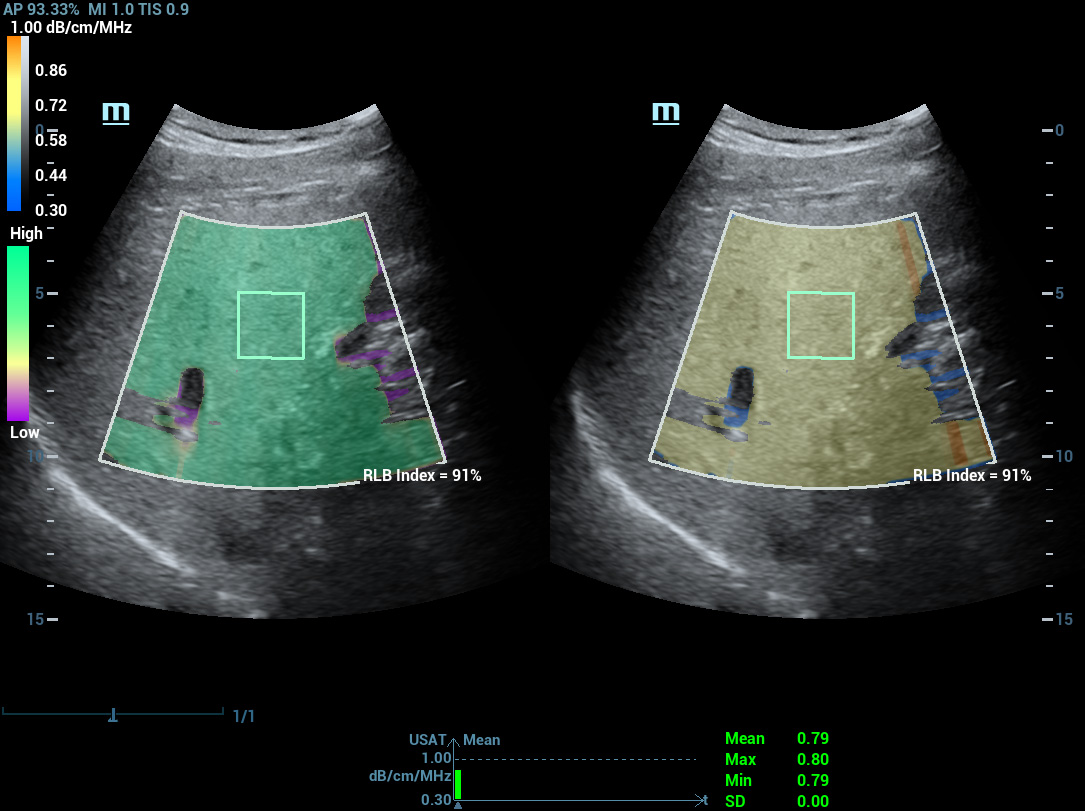

Multi-parametrisch lab voor leververvetting

Een sprong vooruit in het onderzoek naar steatose

Multi-parametrisch lab voor leververvetting

Het multi-parametrische lab voor leververvetting biedt meerdere tools voor kwantitatieve analyse die gebaseerd zijn op verschillende akoestische technologie?n. Het maakt een kwantitatieve analyse van steatose mogelijk en verbetert de gevoeligheid van de detectie van leververvetting in een vroeg stadium.